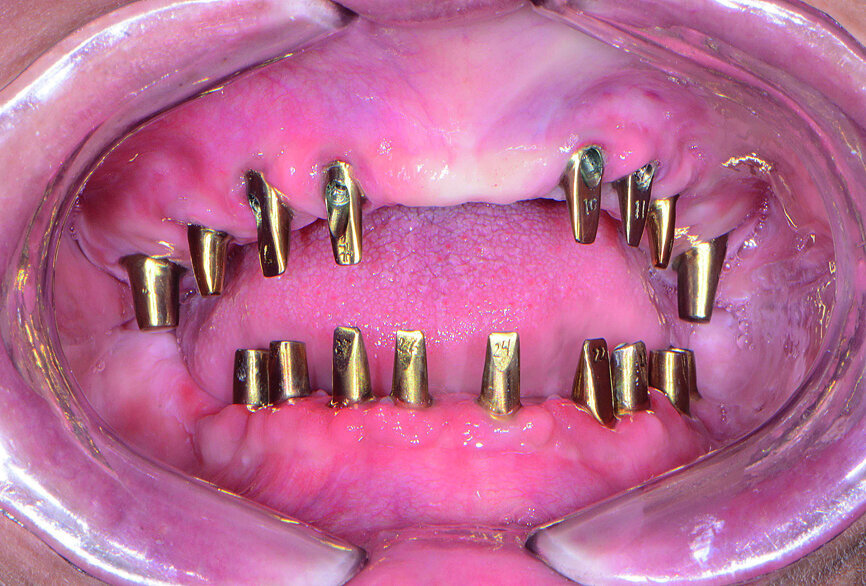

Fig. 19: Inclusive CAD/CAM abutments.

The patient returned for clinical evaluation of the prosthetic design. The custom abutments were delivered using laboratory-provided acrylic delivery jigs, which helped ensure proper orientation during seating (Fig. 19). Owing to the precision of the digital design process, the fit of the custom abutments was ideal, establishing margins that were at or a slight distance from the gingival surface. This simplified the removal of excess cement from the margins and illustrates the advantages of CAD/CAM produced abutments.

The PMMA Smile Composers were seated over the custom abutments, and slight alterations were made to fine-tune the gingival margins, length of teeth, and bite (Fig. 20). A bite registration was taken with the try-in bridges in place.